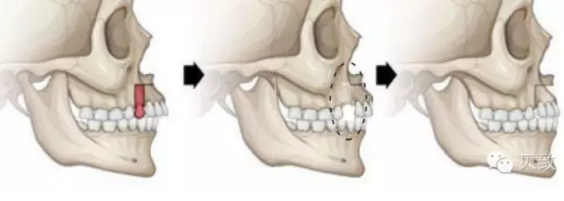

(2)怎么看嘴巴都很凸?拔牙矯正對(duì)側(cè)貌改變有可能是“翻天覆地”的:

撐起人們面部輪廓的主力是下頜骨、顴骨和唇頰軟組織,正畸對(duì)正面臉型的改變相對(duì)較小,但是!正畸對(duì)側(cè)貌改變有可能是“翻天覆地”的!

雙牙弓前突、齙牙、地包天等癥狀引起嘴型突出的寶寶們,可以通過(guò)拔牙獲得間隙,以達(dá)內(nèi)收前牙、前移后牙,影響牙齒周?chē)齑侥橆a的肌肉和軟組織形態(tài)變化,使原本外凸的嘴型得到改善,獲得穩(wěn)定、平衡、美觀的面部側(cè)貌。